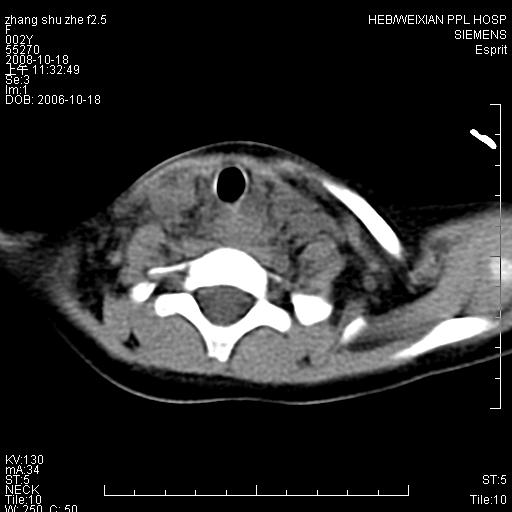

以下是引用dyqct在2009-2-10 21:04:00的发言:[br]年龄?性别?有发烧吗?[br]鼻咽部、口咽部、喉咽部及颈椎前间隙广泛肿厚,明显占位效应并致相应组织变形。ct值22-28hu。[br]考虑:1、颈前脓肿可能性大;[br] 2、建议增强或治疗后复查。

以下是引用jiangjing在2009-2-11 11:37:00的发言:[br]急性病程,鼻咽部、口咽部、喉咽部及颈椎前间隙广泛肿厚,明显占位效应并致相应组织变形.考虑颈部感染性病变(脓肿?);建议行进一步检查。